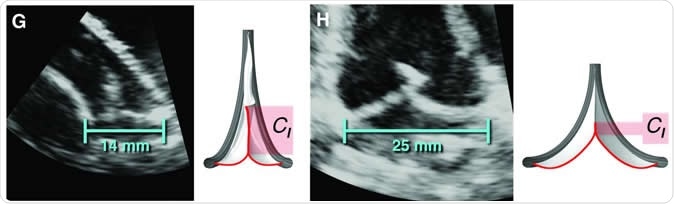

The valve replacement expanding to accommodate different lengths in implanted sheep. This material relates to a paper that appeared in the Feb. 19, 2020, issue of Science Translational Medicine, published by AAAS. The paper, by S.C. Hofferberth at Boston Children

The valve replacement expanding to accommodate different lengths in implanted sheep. This material relates to a paper that appeared in the Feb. 19, 2020, issue of Science Translational Medicine, published by AAAS. The paper, by S.C. Hofferberth at Boston Children's Hospital in Boston, MA; and colleagues was titled, "A geometrically adaptable heart valve replacement." Image Credit: S.C. Hofferberth et al., Science Translational Medicine (2020)